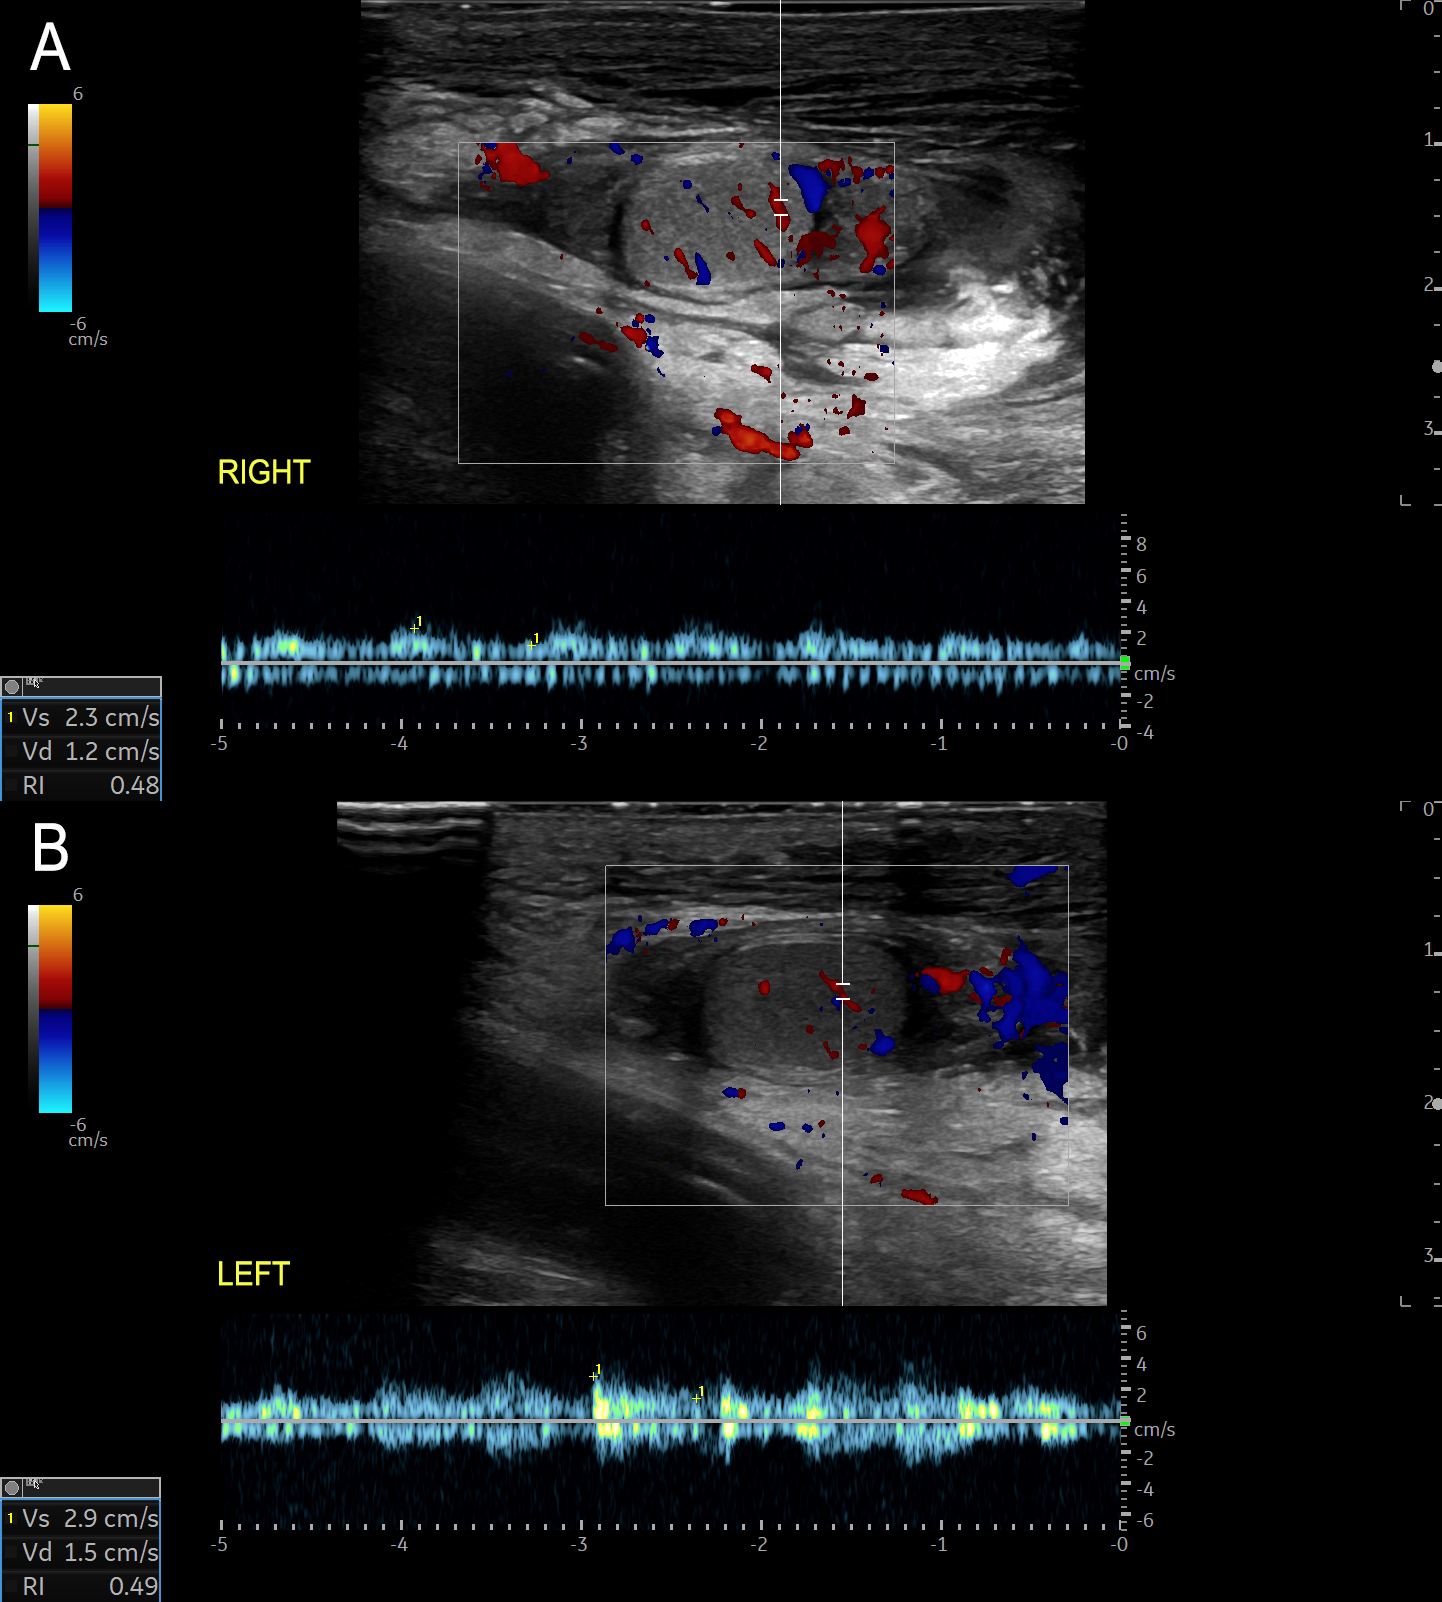

A 7-year-old boy, with no significant medical history, was admitted with complicated acute appendicitis and underwent an appendectomy. Two days after surgery, he developed painless, marked scrotal swelling. Physical examination revealed significant scrotal edema and erythema without tenderness. Ultrasound (US) showed diffuse hypoechoic thickening of the scrotal wall and pronounced subcutaneous edema, while the testes and epididymis appeared normal (Figure 1). Doppler imaging demonstrated marked bilateral hypervascularity in the scrotal wall, including the "fountain sign" (Figure 2), with normal intratesticular blood flow (Figure 3). These findings were consistent with acute idiopathic scrotal edema (AISE). The patient was managed conservatively with anti-inflammatory and antihistamine medication. The edema entirely resolved after four days, and a follow-up US confirmed the resolution of hypervascularity and edema.

From a radiological perspective, the diagnosis of AISE is often established using US, which is the modality of choice due to its non-invasive nature and high sensitivity for scrotal pathology.2 US findings typically include diffuse thickening of the scrotal wall and marked subcutaneous edema, with unremarkable testes and epididymis.1,2 Doppler imaging can further confirm the absence of testicular torsion by demonstrating normal intratesticular blood flow.3 A distinctive feature observed on Doppler imaging in AISE is the "fountain sign", characterized by hypervascularity in the scrotal skin and dartos fascia, due to increased flow in the anterior and posterior scrotal arteries.3 This sign is considered a hallmark of AISE. It helps to differentiate it from other causes of acute scrotal swelling, such as epididymitis, orchitis, torsion of the appendix testis or testicular torsion, which usually present with more severe clinical symptoms and abnormal testicular findings on imaging.3